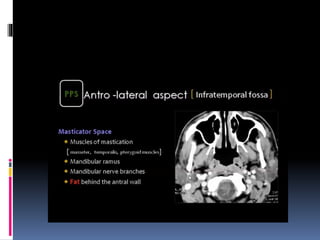

 The fissure between the orbit and the

maxillary sinus i.e. the INFERIOR ORBITAL

FISSURE is seen in this cut.

 The INFERIOR ORBITAL FISSURE opens into

the INFRATEMPORAL FOSSA